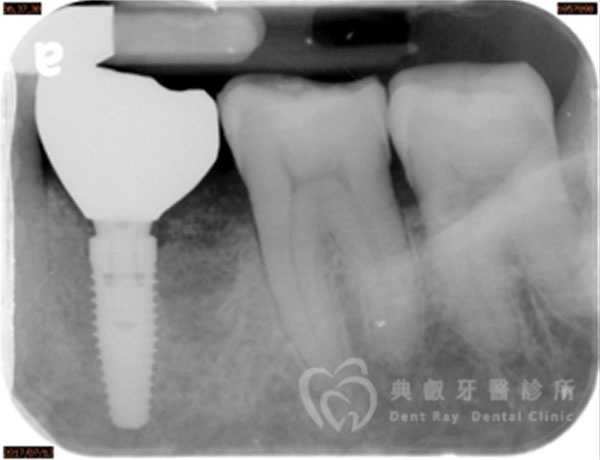

植牙案例一